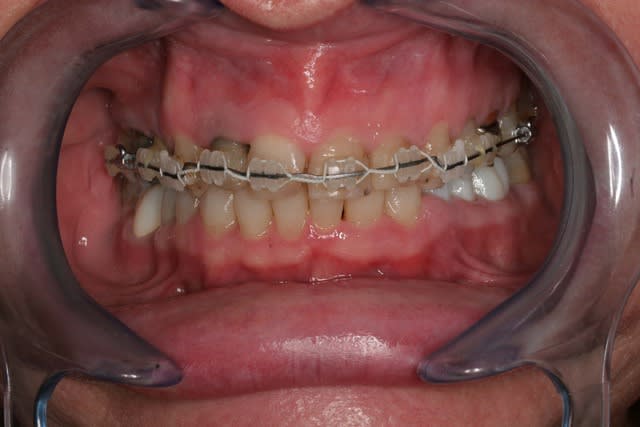

Donc la suite, évidement ortho: ingression du bloc incisivo canin sup avec ré alignement des arcades, extraction de la 14 nécessaire et ré alignement des milieux interincisif.

Pendant la finalisation du haut (axe mésio-disto incisif, à corriger à la fin pour faciliter gingivoplastie incisif sup). Il y a eu composite vestibulaire pelliculaire sous digue de 33 à 43, reprise soins et ancrage + provisoires 34,35, 36, 46; et composite sous digue 37 et 47.